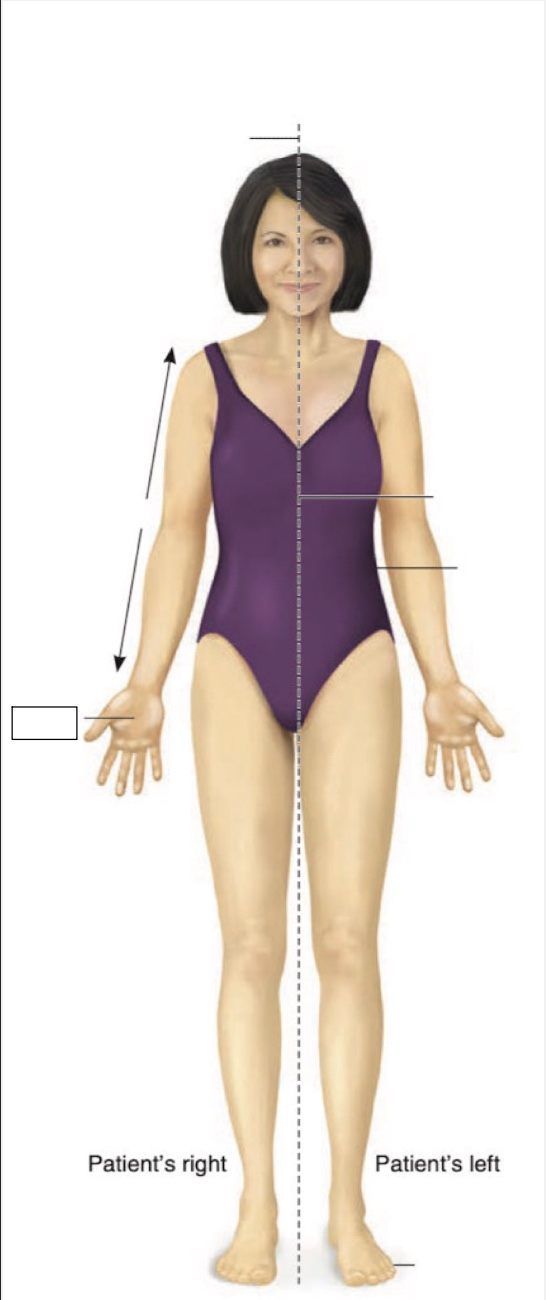

Posterior

Anterior

Superior

Inferior

Midline

Proximal

Distal

Palmar

Medial

Lateral